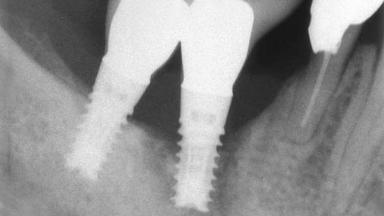

Peri-implantitis Resulting in Bisphosphonate-related Osteonecrosis of the Jaw

A 82-year-old female patient was referred to the Department of Oral Surgery and Stomatology at the University of Bern, Switzerland, for further diagnosis and treatment of growing discomfort in the right mandible (implant 45) and left maxilla (implant 23). The patient had had implants of various types inserted in the mandible and maxilla over the course of the previous three decades (in the 1980s and 1990s). The patient had received removable partial dentures on implants in the maxilla and on natural teeth in the mandible. The implants in the posterior right mandible had been restored with two splinted single crowns. The lower partial denture was not well tolerated by the patient and therefore had not been worn for over ten years. After insertion of the implants, there had been no complications for many years, but implants 45 and 46 as well as 23 had begun to exhibit signs of peri-implantitis with limited bone loss several years previously. The infection had been treated by the private practitioner, and bone loss around the three implants had not progressed until about half a year previously.